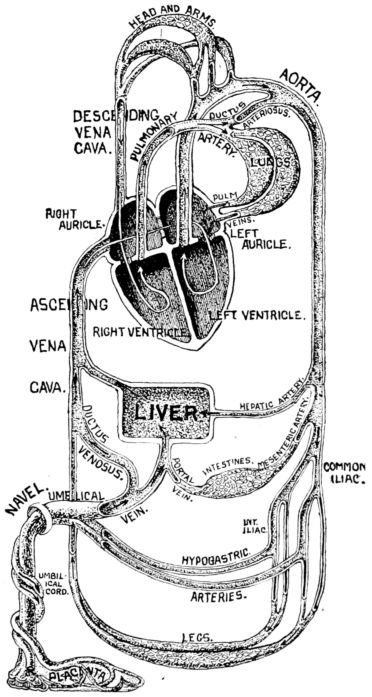

| xx28. | Diagram of fetal circulation | 85 |

| 29. | Diagram of circulation after birth | 87 |